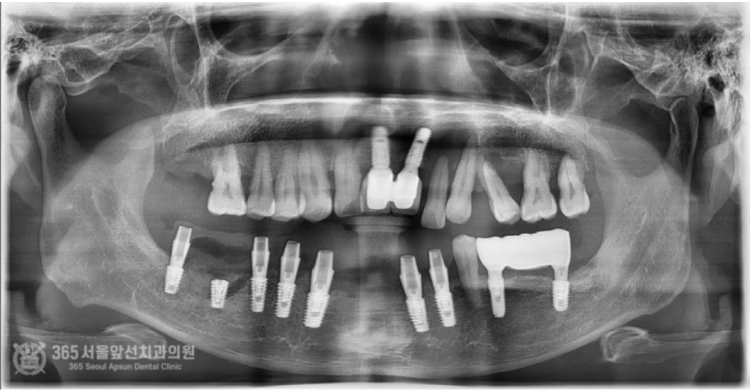

안녕하세요. 도화역치과 365서울앞선치과입니다. 오늘 소개해 드릴 치료 증례는 지인분의 소개로 찾아오셨던 환자분이십니다. 전체적으로 치아가 좋지 않으나 일단 아랫턱부터 치료를 완료하고 나서 윗턱을 치료받고 싶다고 하셨습니다. 바쁘게 사회생활을 하셔야 하는 환자분이셔서 발치와 동시에 뼈이식을 진행하며 임시치아까지 즉시 만들어 드렸습니다 ㅎㅎ 촬영일시: 2024.06.20. 처음 도화역치과 365서울앞선치과에 내원하셨을 당시 엑스레이 사진입니다. 전체적으로 잇몸뼈 소실 증상이 있고 치아 상태가 매우 좋지 않습니다. 일단 위쪽은 아래쪽 치료를 마무리 한 이후에 하기로 결정하셨습니다. 촬영일시: 2024.07.06. 발치와 동시에 뼈이식을 진행하면서 임플란트 식립까지 완료한 이후 엑스레이 사진입니다. 가지런히 식립된 임플란트 보기 좋습니다 ㅎㅎ 수술시간은 대략 30분 정도 걸렸습니다.